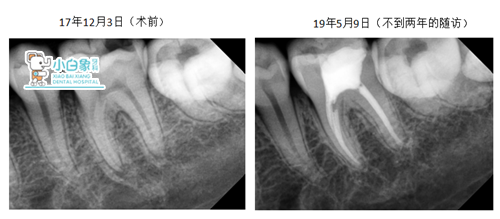

根尖暗影未见明显增大,在逐渐缩小

摘自北京大学口腔医学院:根管治疗的成功因素中除了对

感染物质的处理与控制外,最主要的还有根管治疗后的冠

方及时修复,达到良好的封闭。一项临床研究表明,在根管

治疗失败的病例中,有约60%与冠方修复不良有关。牙髓病

与牙髓一体化治疗,强调诊断,设计,根管治疗,牙体修复

和疗效追踪由同医师。